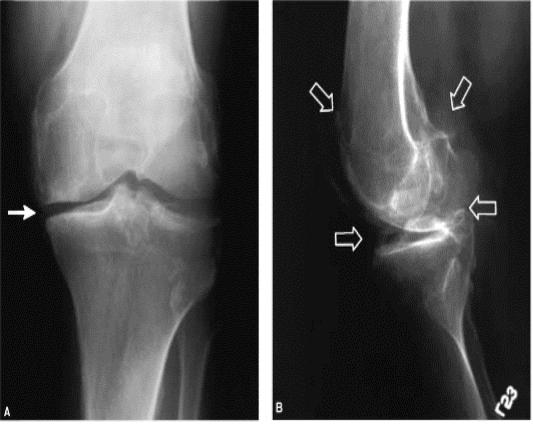

Рентгенограммы коленных суставов представлены на рисунке

1.Какие изменения видны на рентгенограммах?